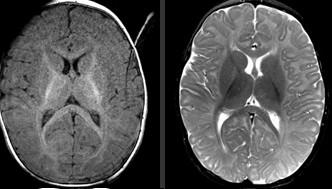

Sweep the Midline: What parts are missing?

Run the Rim…where is the cortex “too thick?”

“Missing”=disorganized rostrum, genu, anterior body of the corpus callosum Cortex of the anterior medial frontal lobes “too thick” with fused grey matter across the anterior midline where the “genu” should be.